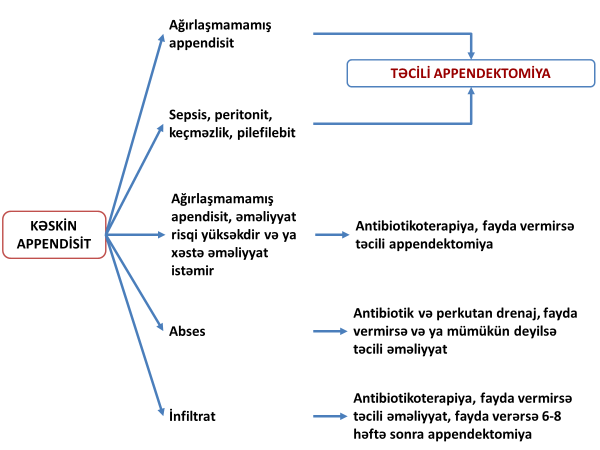

Kəskin appendisitin standart müalicəsi açıq və ya laparoskopik appendektomiyadır. Bu prinsipdən nadir istisnalar var: infiltrativ appendisit, əməliyyat riski çox yüksək olan xəstələrdə ağırlaşmamış appendisit əlamətləri. Son illər ağırlaşmamış appendisitlərdə antibiotikoterapiyanın faydalı olduğu barədə məlumatlar var.

Şəkil 4. Kəskin appendisitdə müalicə yanaşması